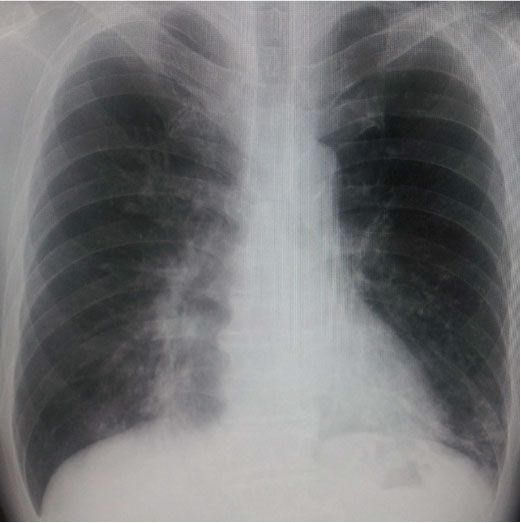

<画像所見>

・胸部Xp:両下肺野に浸潤影、粒状影